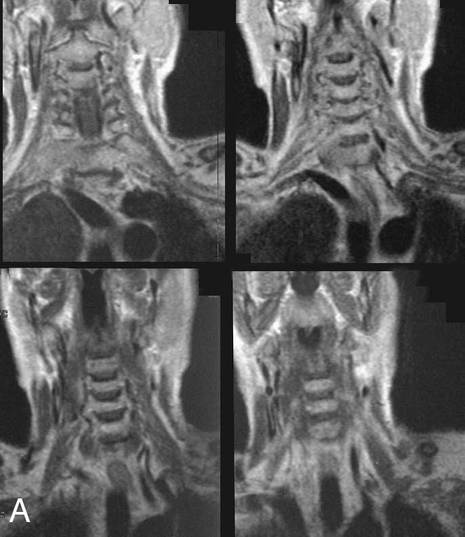

Image A below shows an abnormality on coronal T1-weighted MR in the region of the anterior scalenes.  Image B shows the same CT with structures outlined.

This patient has a lung cancer that has metastasized to C7 and is growing out to the right, invading the region of the brachial plexus and causing arm pain and weakness.  The tumor is shown in red.  The middle and posterior scalene muscles, which pass posterior to the brachial plexus, are outlined in yellow.  The bracheal plexus is outlined in green.  The anterior scalenes are outlined in blue.